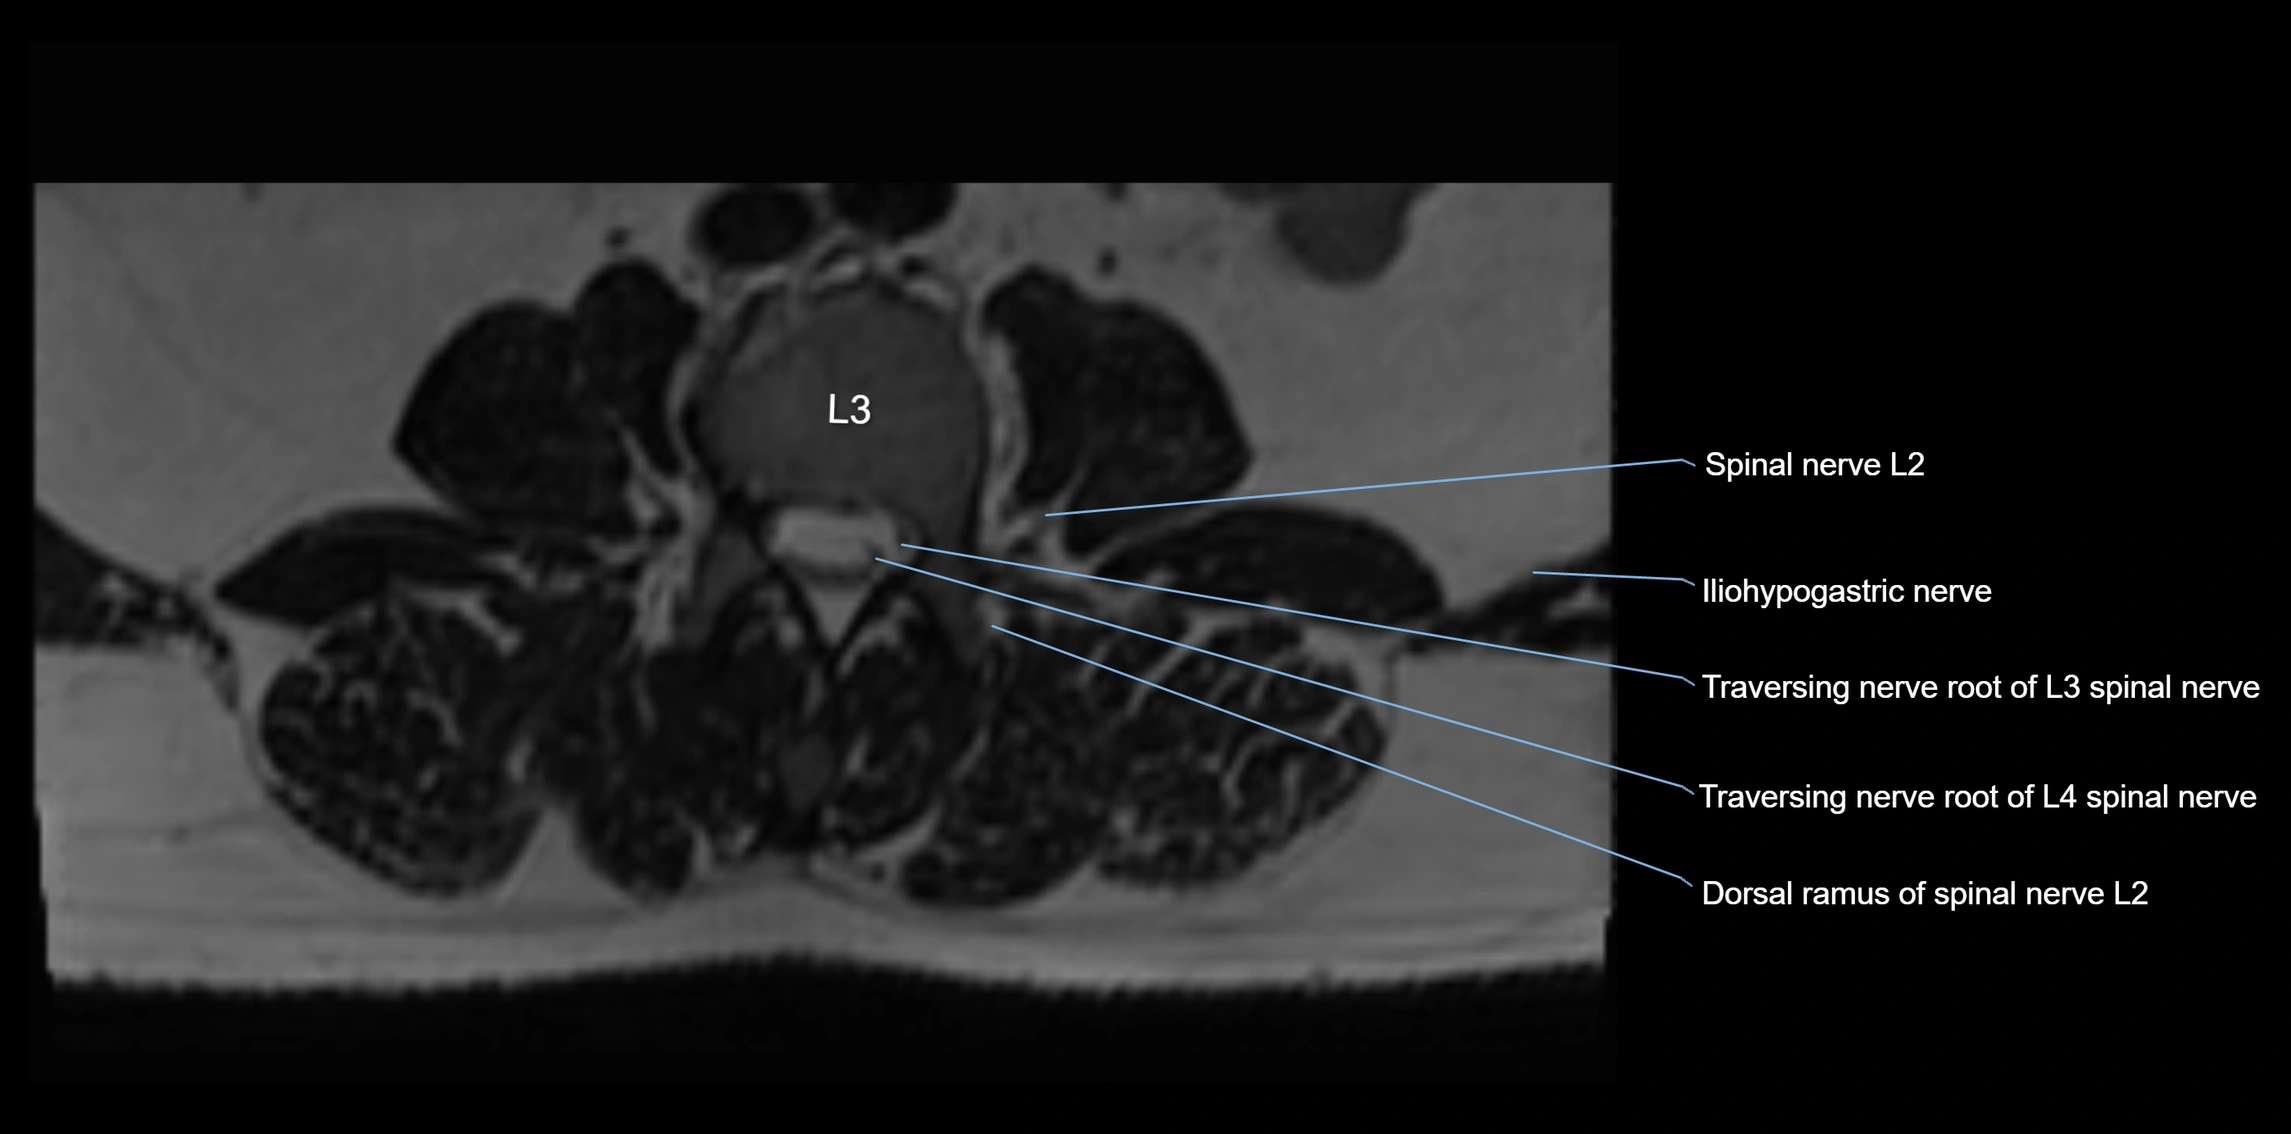

MRI image

image